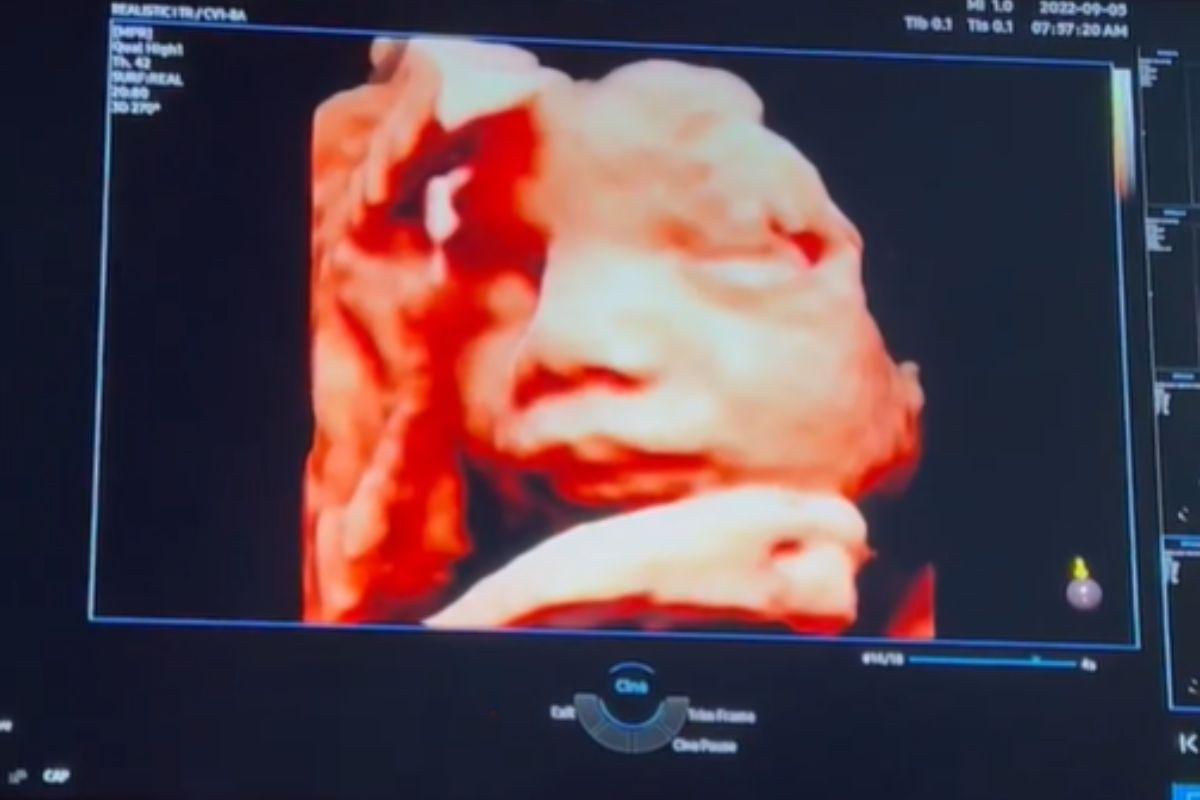

Gabriela Pugliesi mostra rosto do bebê pela primeira vez em ultrassom: “Bochechudo!”

Nesta segunda-feira, 5 de setembro, Gabriela Pugliesi mostrou aos seguidores através das imagens de ultrassom pela primeira vez o rosto de Lion, seu primeiro filho, fruto do relacionamento com o rapper Túlio Deck. Pelas imagens ela comentou sobre como está encantada com o rosto do bebê e também comentou sobre a posição que ele está: “Meu bebezão bochechudo! Está quase encaixado, tudo perfeito”.

Além de mostrar as atualizações da espera do primeiro filho, Gabi Pugliesi também derreteu seus seguidores com detalhes do rosto de Lion: “Não consigo me concentrar com essas imagens. O que eu faço? Olha essa primeira, o bico”. A influencer, que está no sétimo mês da gestação, contou recentemente que engordou nove quilos durante a gravidez, mas isso muito pelo contrário do que se especulava, não incomodou Gabi. “Ganhei umas celulites também. E nunca me senti tão linda. Estou numa nova relação com o meu corpo. Sem cobrança, sem meta, só sentindo e vivendo. Nosso corpo é mágico. Vejo tudo isso como uma bênção”, contou Gabi aos seguidores.